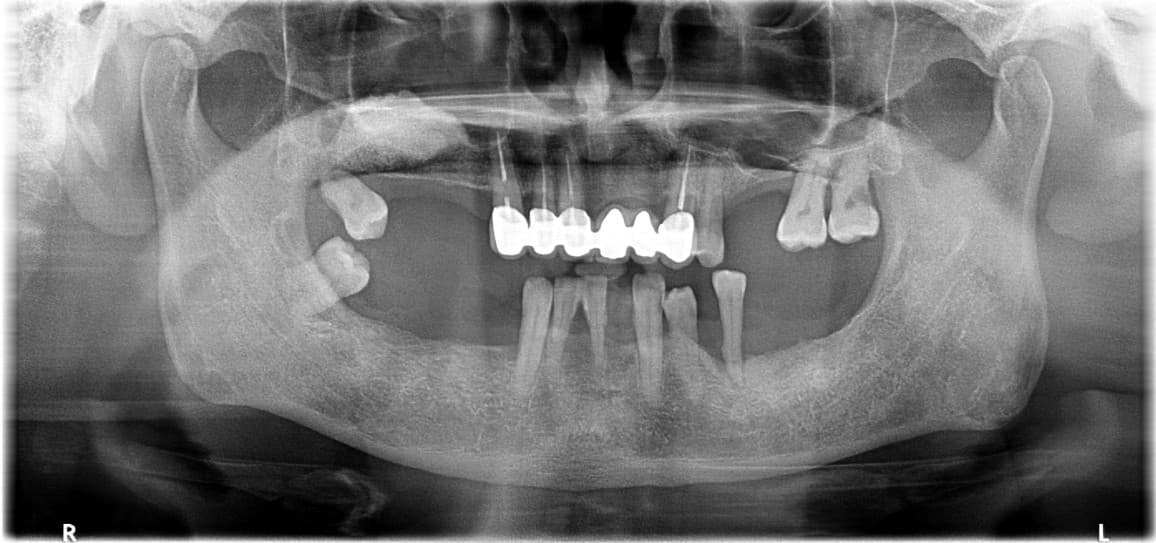

Full Mouth Reconstruction · Mr. S●● · Male, 70s

Full Mouth Reconstruction · Mr. O●● · Male, 60s